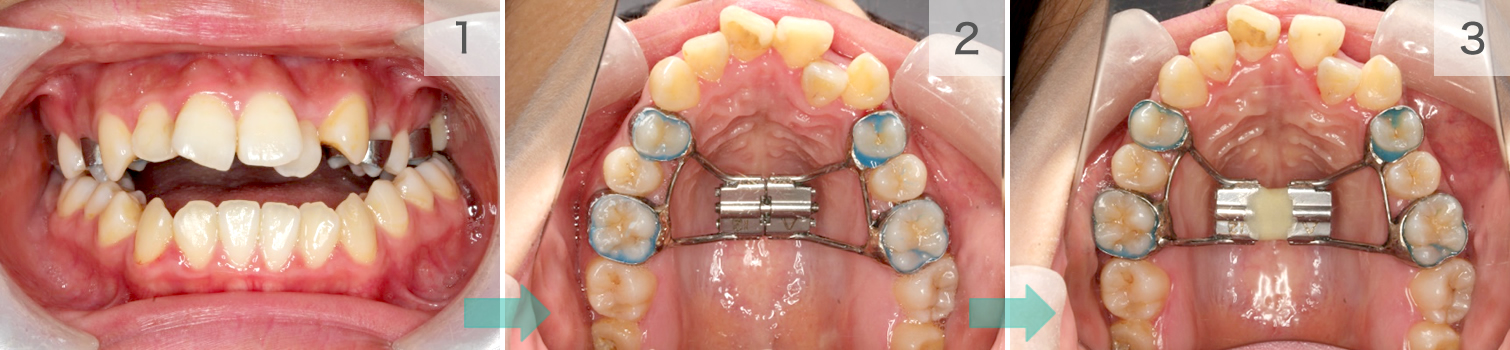

症例01. Sectional

混合歯列期や限局矯正に、ブラケットとワイヤーを用いて

並べます。凸凹だけでなく、噛み合わせの深さなども変え

られます。

| 治療内容 | 1:すきっ歯と八重歯が気になる 2:まず前歯を閉じる 3:スペースを使ってきれいに並べる |

|---|---|

| 期間 | 半年~1年 |

| 費用 | 300,000円+税 |

| リスク | 歯の動きに伴ったむずがゆさや軽度の痛みが出る可能性があります。 数日程度で慣れてしまいます。 |